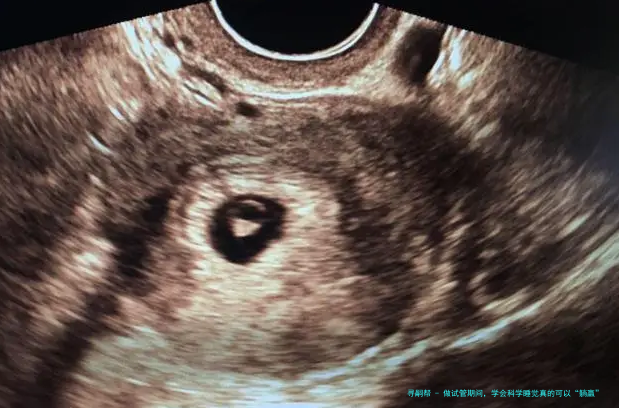

⑴在促排卵期间,可以适当多休息,但是预防长时间坐、久卧等情况,影响到身体健康和促排卵效果。促排卵用药后,女性的卵巢内多颗基础卵泡的发育,以及内里激素水平发生变化,此时女性可能会有萎顿感,可分频繁短暂时间地坐卧休憩,但是应注意掌控时间,并且按时用饭和如厕。按时睡醒活动身体,不仅有益于身体血液的反复,还可改善胃口,提高卵巢对促排用药的反响,从而提高获卵数目和素养。于采卵术后要躺床休息6—8小时,随后就可以痊愈正常的生活,纪律作息、做好卫生管理防备创口感染、避免身体疲劳和激烈运动就可以。